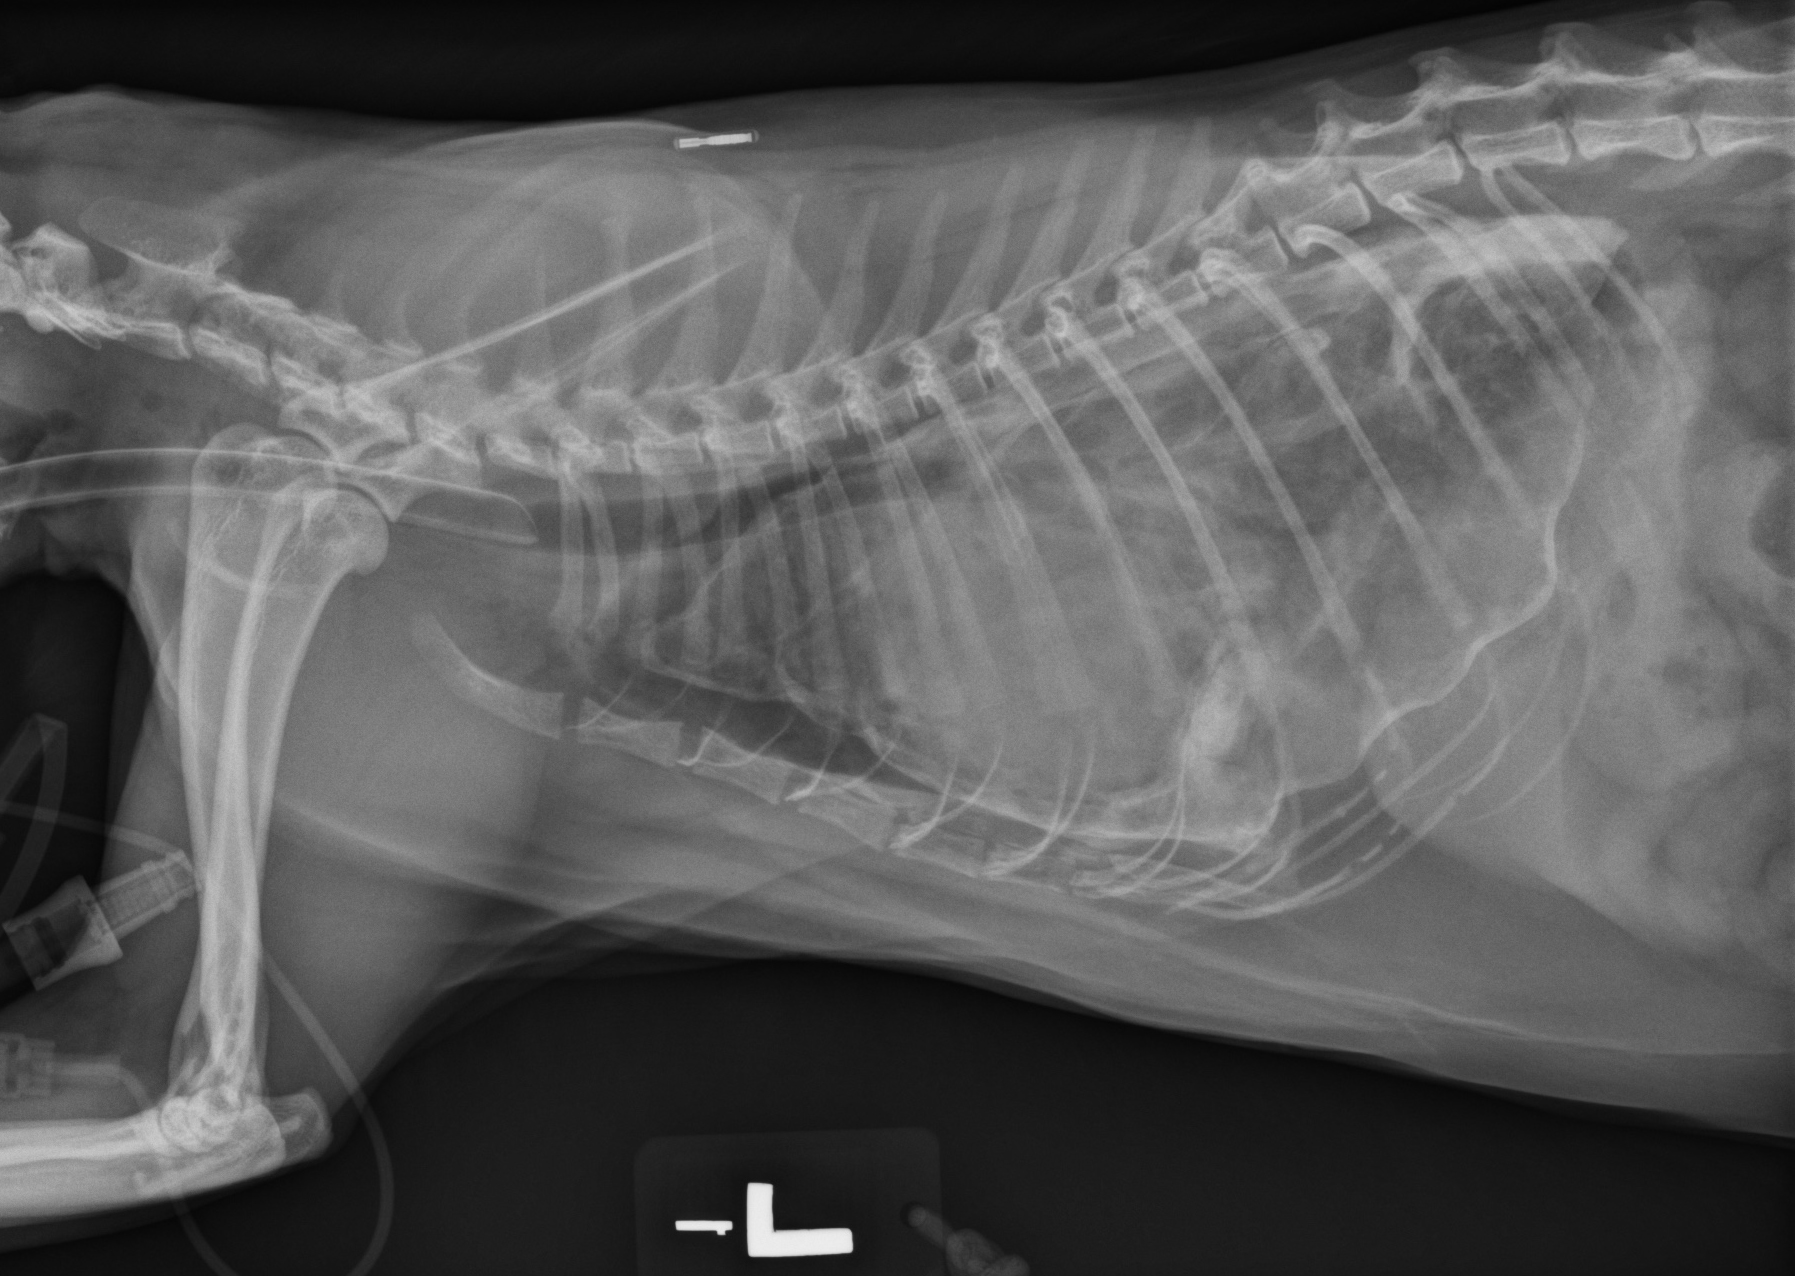

Latérale gauche